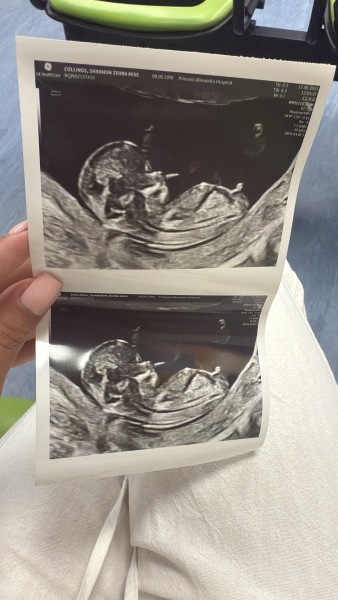

Girlmam1517 · 31/01/2025 11:15

I am pregnant with my 3rd baby and me and my husband have 4 girls between us, I have posted my scan photo across numerous nub theory pages and sent it off to a professional site! All have said girl. I got my gender scan in 2 weeks and I'm scared that they are going to say girl aswell, as we are all (including the girls) hoping for a baby boy 😩 my girls are going to be so upset, I just know it.

Has anyone had nub theory be wrong?

Girlmam1517 · 31/01/2025 11:33

Early glimpse have come back with 99.9% girl for me, I got a gender scan in 2 weeks, praying they are wrong 🤞🏻 4 girls between us, and even the kids are hoping for a boy